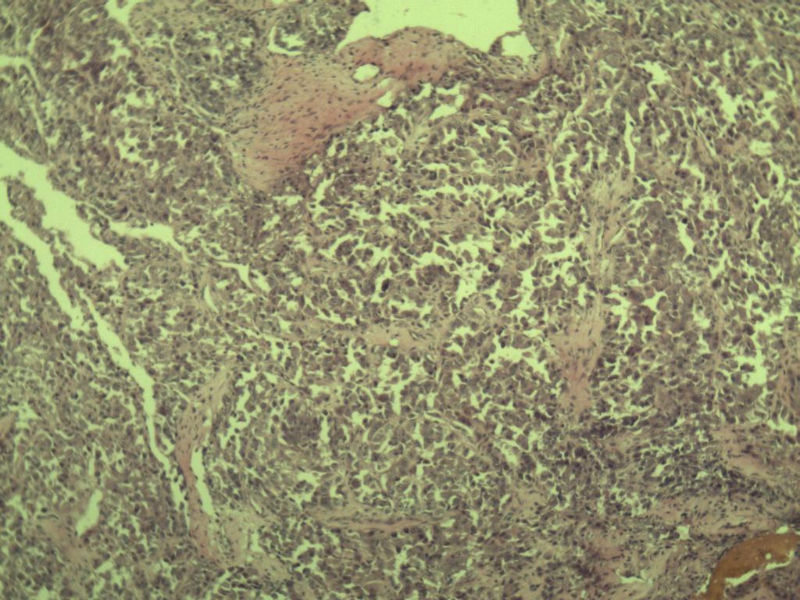

女 70岁 右颈部 头皮 多发皮下结节      取颈部部分结节送检 灰白小组织 1 块,直径 0.4 cm。 请问这个是什么?

肿瘤细胞大,上皮样,核空泡状,核仁明显,胞质嗜酸性或透明。

考虑:恶性黑色素瘤?

近心型上皮样肉瘤?

软组织透明细胞肉瘤?

上皮样多形性脂肪肉瘤?

等免疫组化标记!

此片染色欠佳,取材或切面也有问题,加大了诊断的难度,恶黑确实需要考虑,但其他一些转移癌也需要排除,比如肺癌之类的,还是期待免疫组化!